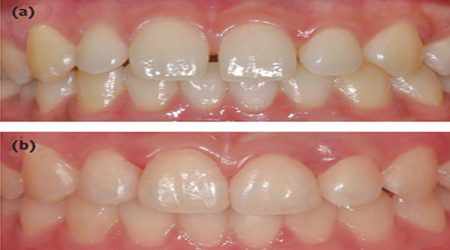

Child Dentistry

Smile For Children

Fluoride Gel Application 2100 30

Fluoride Varnish (1-6 Teeth) 1200-1500 15-25

PIT & Fissure Sealant 1100 15

Orthodontic Appliances (Wires,Plates,Braces) 10000-15000 150-200